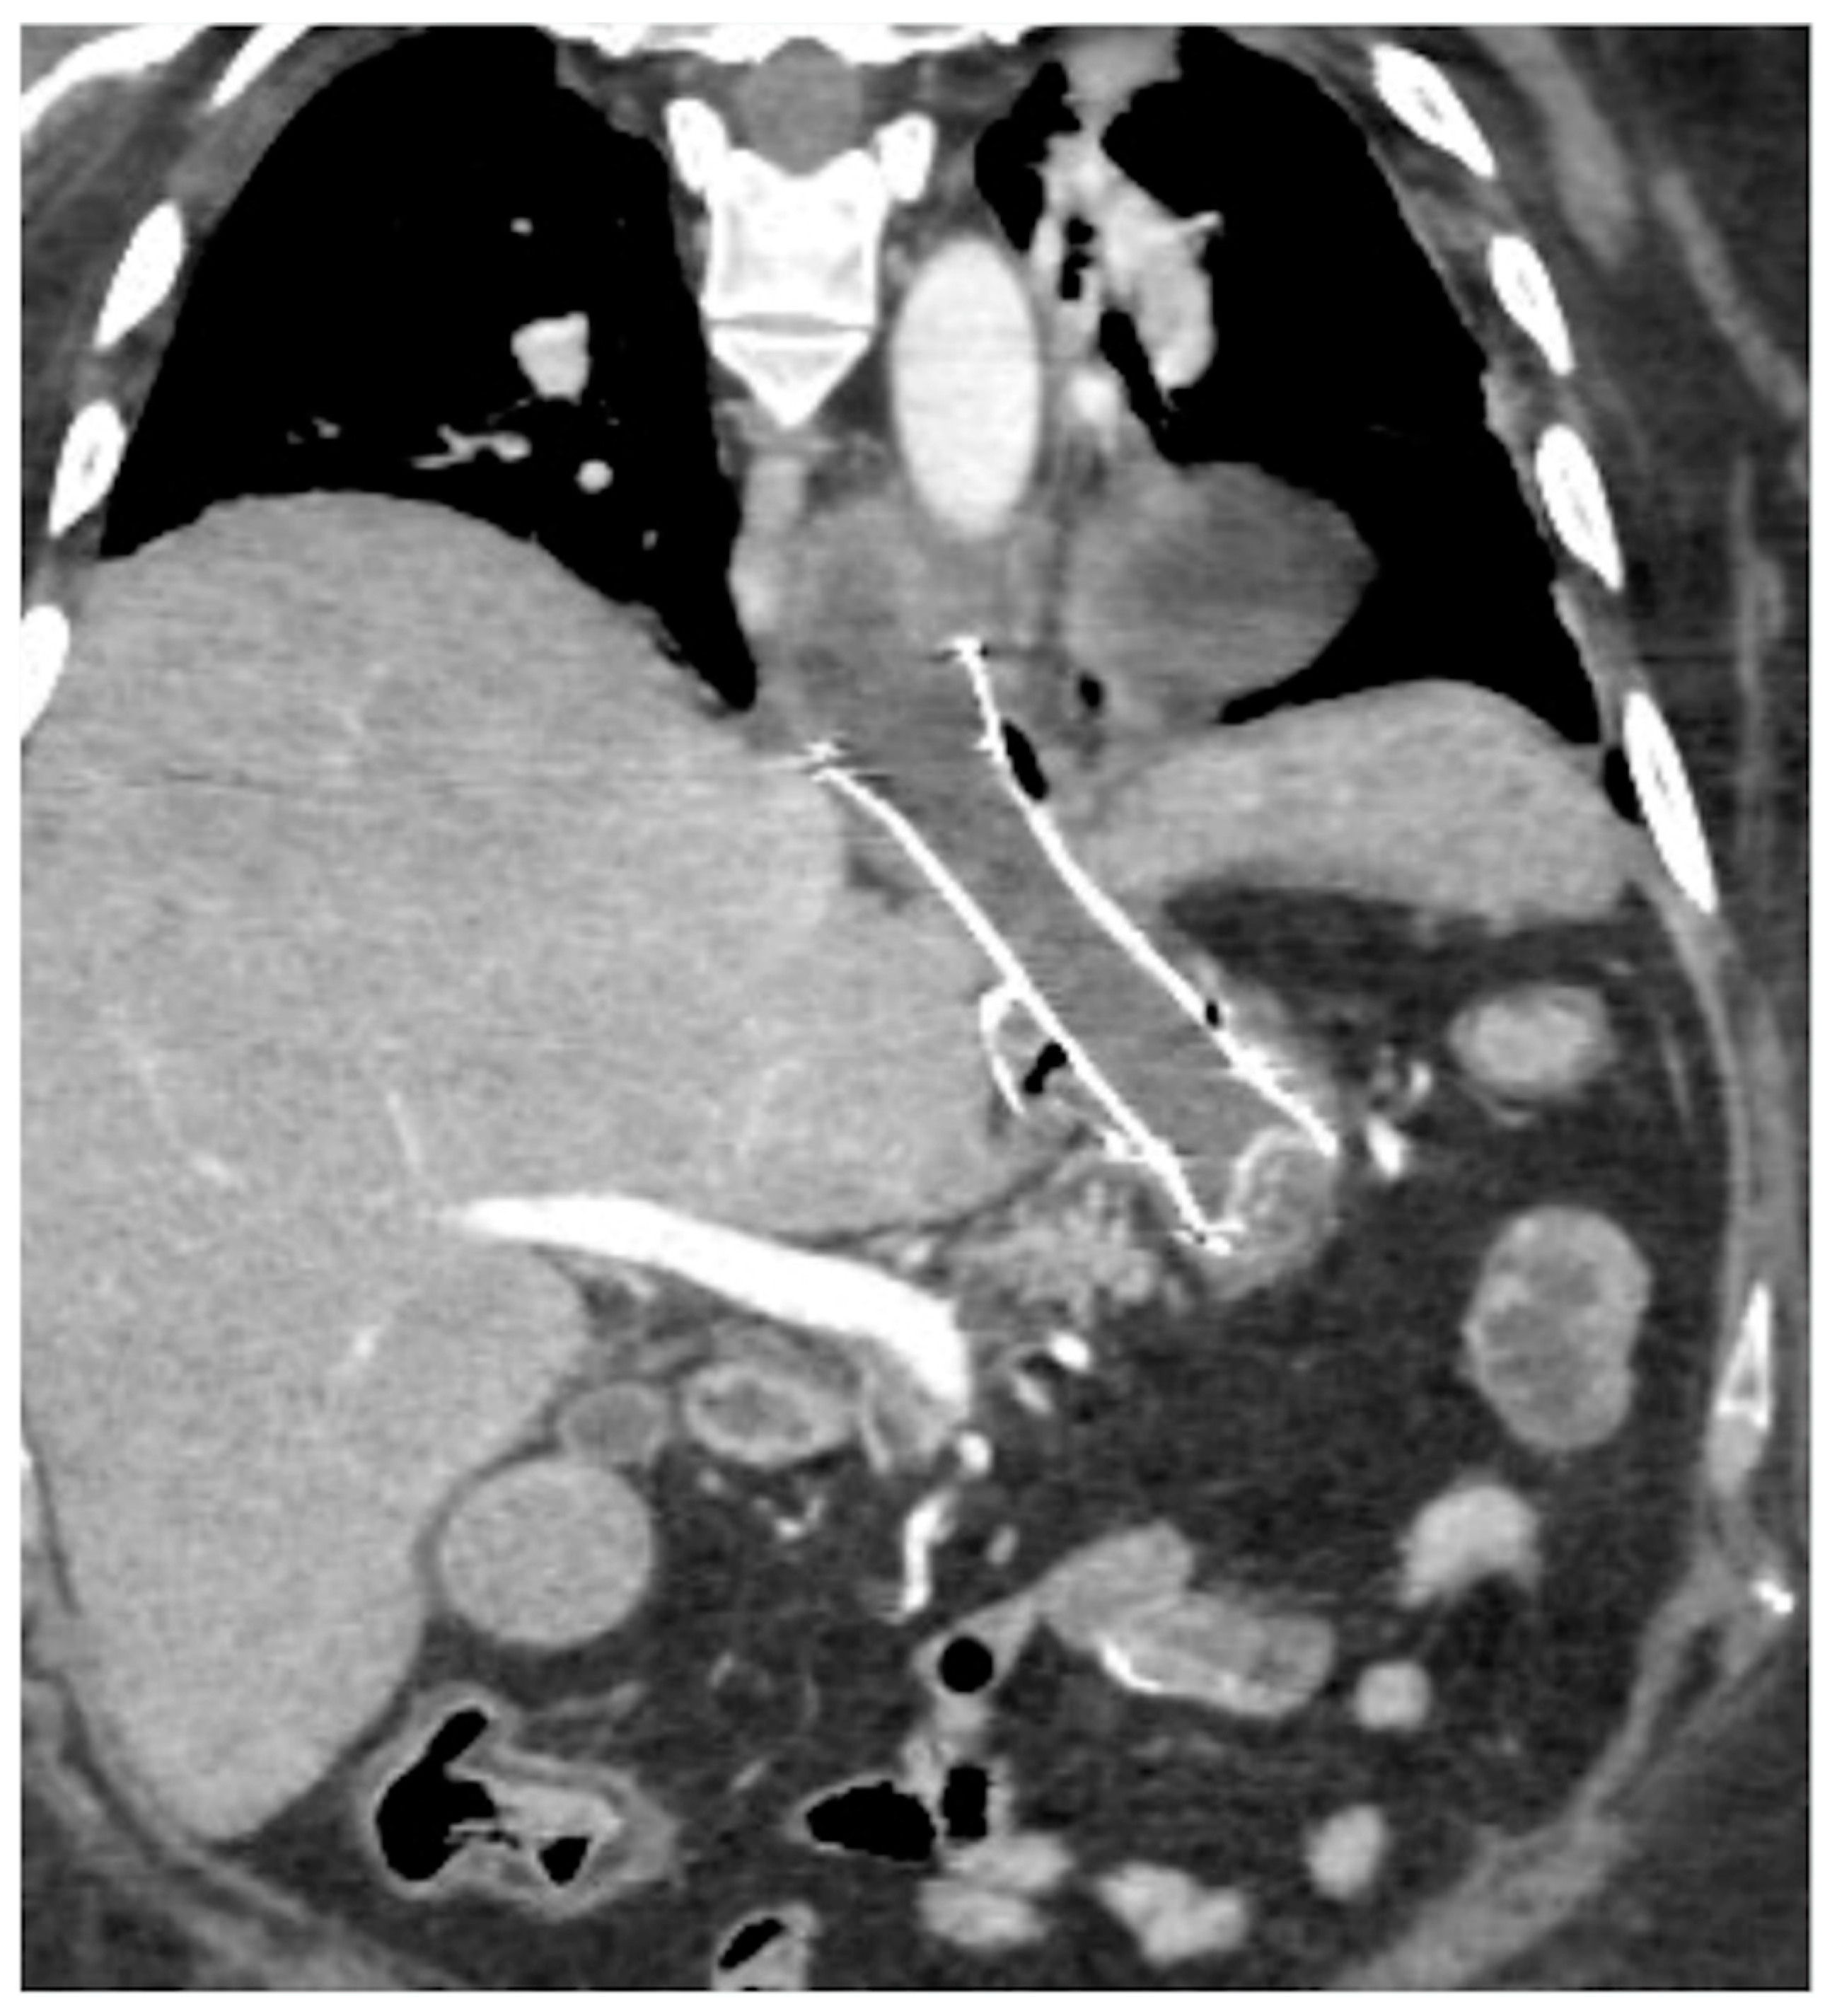

Figure 15. Spleno-portal thrombosis and liver abscesses after sleeve gastrectomy with suture leak. A 46-year-old female with a type I leak after sleeve gastrectomy complained of abdominal pain, fever and kidney failure. Note the gastric surgical suture (a, coronal oblique view), the presence of a type I leak (b, axial view, straight arrow), and of multiple liver abscesses (bd, axial view, curved arrows) related to extensive spleno-portal thrombosis (df, straight arrows). The leak is responsible for spread of gastric content and bacteria, causing septic spleno-portal thrombosis and, consequently, liver abscesses. The leak was conservatively treated and the thrombosis was successfully treated with multiple sessions of transhepatic catheter-directed thrombolysis.